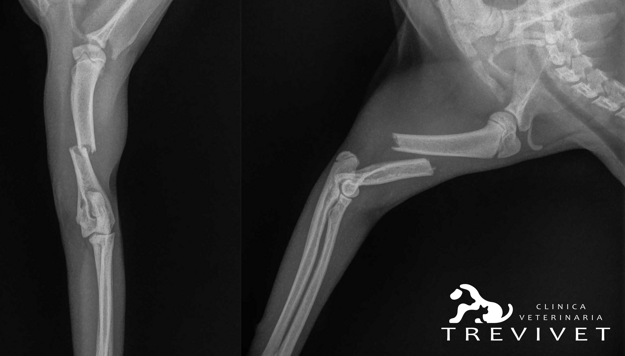

Favy gattina comune europea di circa 6 mesi, viene portata in visita per una zoppia di 4° grado sull’arto anteriore destro. Alla visita si nota un accorciamento dell’arto più marcato nella zona prossimale con supinazione della mano e mantenimento del dolore profondo.

All’esame radiografico in sedazione si evince la presenza di una frattura trasversa dell’omero del 2° terzo medio con contrazione e dislocazione mediale del moncone distale.